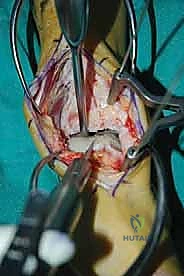

الغوص العميق في جراحة الطعم الخيفي الهيكلي (Structural Allograft Reconstruction)

يهدف هذا الإجراء العبقري إلى استبدال الغضروف والعظم التالفين والميتين بنسيج سليم تماماً مأخوذ من متبرع متوفى (طعم خيفي - Allograft). هذا الطعم يتم تعقيمه وحفظه في بنوك الأنسجة العالمية وفقاً لأعلى المعايير الطبية الصارمة لضمان خلوه من أي أمراض معدية والحفاظ على حيوية الخلايا الغضروفية.

- الترميم التشريحي الحقيقي: يسمح باستعادة الشكل الهندسي الدقيق لعظم الكاحل، بما في ذلك المنحنيات المعقدة لكتف التالوس.

- توفير غضروف طبيعي (Hyaline Cartilage): الغضروف المزروع هو غضروف زجاجي طبيعي،